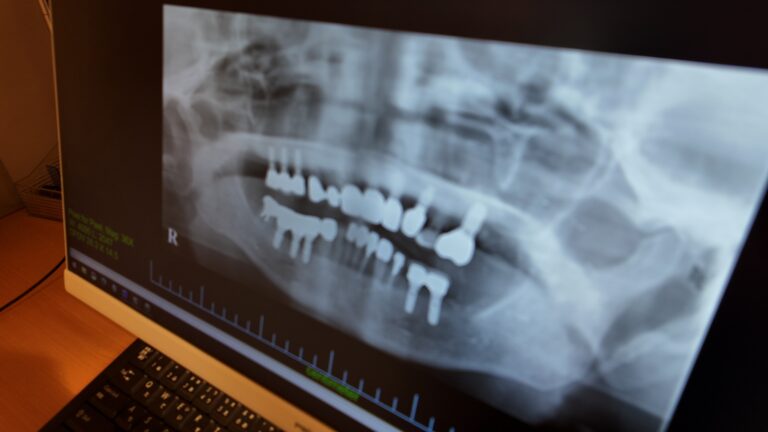

4. 歯科用CTなど精密機器を用いた安全性への配慮

インプラント治療では、骨の厚み・高さ・神経や血管の位置を正確に把握することが重要です。

当院では歯科用CTを用い、三次元的な情報をもとに診断・治療計画を立案しています。従来のレントゲン(2D画像)では把握しきれない情報も確認できるため、治療の安全性に配慮した診療につなげています。

Q3:CTは全員撮るのですか?

CT撮影は、インプラント治療の安全性を高めるために有用な検査の一つですが、すべての方に必ず行うものではありません。骨の状態や治療計画に応じて、必要性を判断したうえで実施しています。

検査の有無や内容については、診察時にご説明し、ご理解をいただいたうえで進めています。